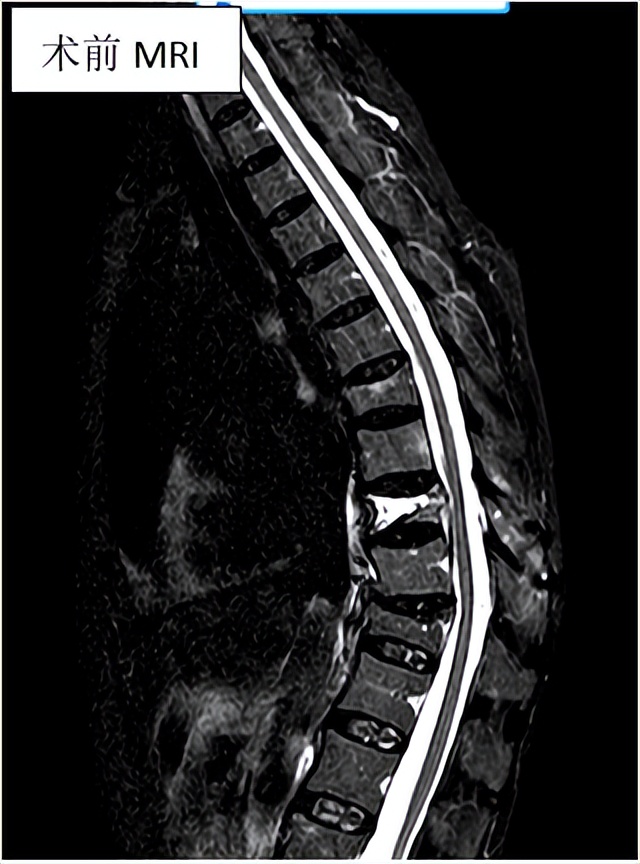

影像学检查

常用的有X线、CT、MRI、骨扫描。